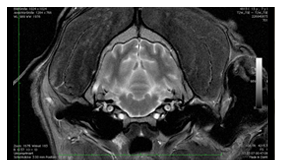

Neurochirurgie

Die Abklärung neurologischer Patienten mittels Computer- und Kernspintomographie (CT- und MRT-Diagnostik) erlaubt die exakte Beurteilung von ​Rückenmark- und Bandscheibenveränderungen und stellt für unsere Chirurgen die Grundlage neurochirurgischer Eingriffe an der Wirbelsäule dar.